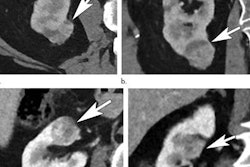

Under the new clearance, the company's Rapid CT-Perfusion and MR-Perfusion software can now also be used by physicians to help select acute stroke patients with known occlusion of the internal carotid artery or proximal middle cerebral artery for endovascular thrombectomy, according to the vendor.